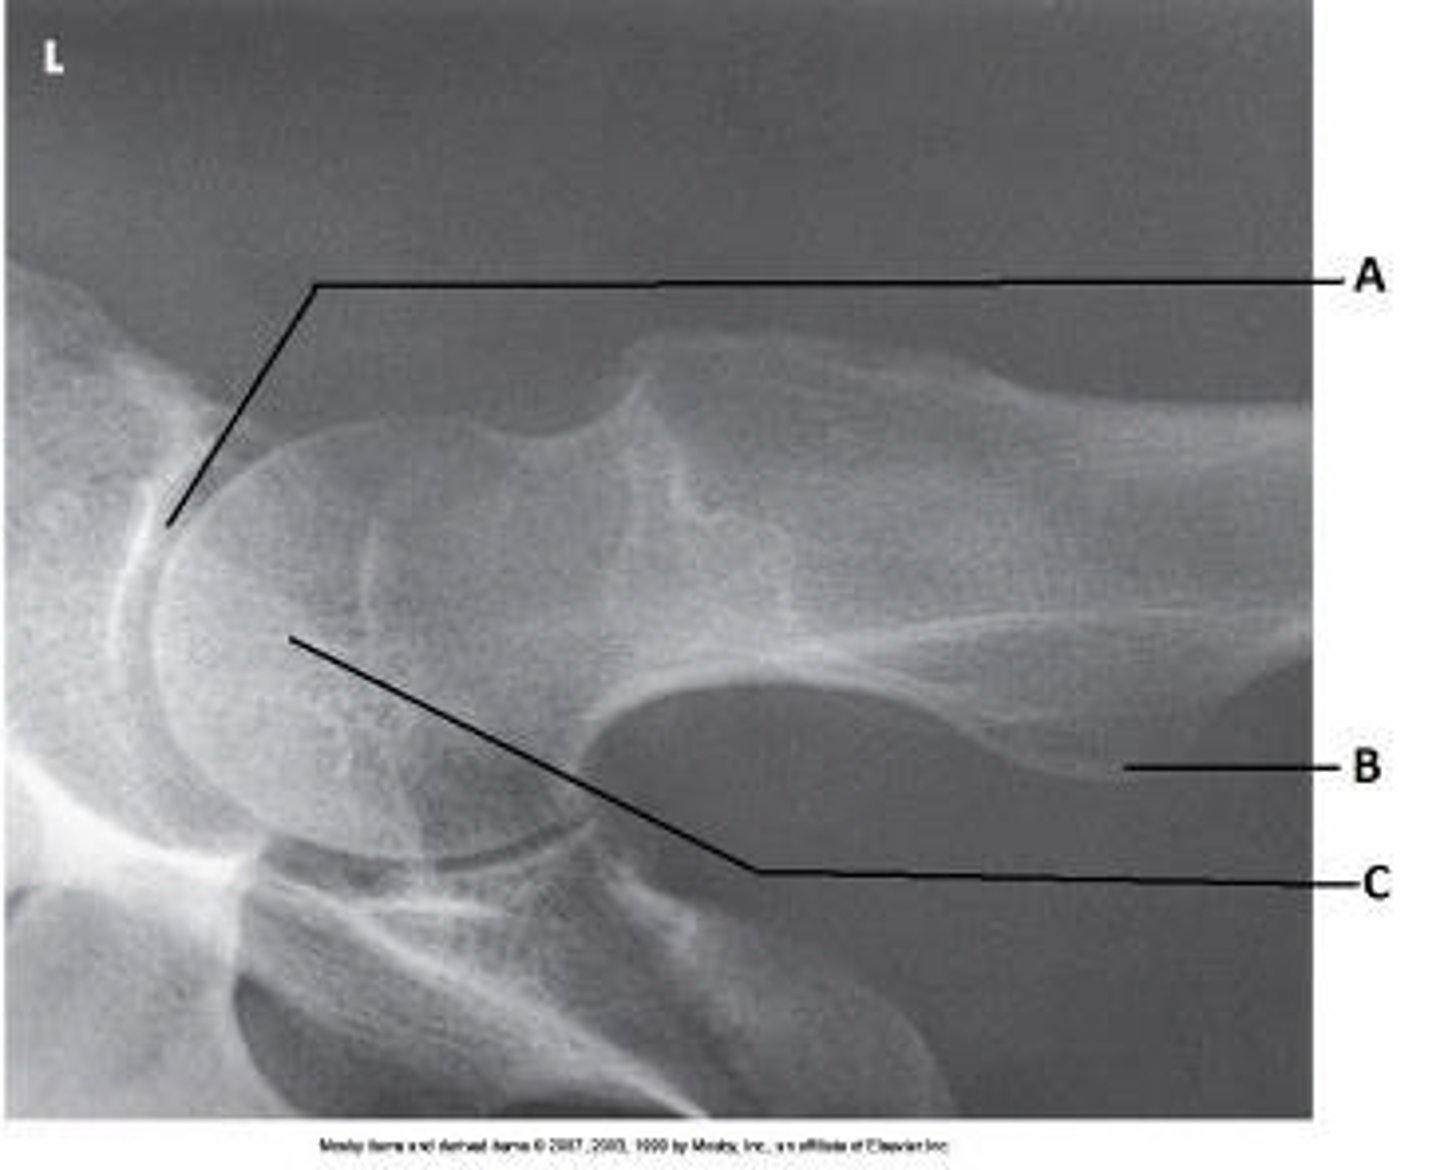

Identify the projection:

AP Hip

Axiolateral Hip (Danelius-Miller)

AP oblique hip (Modified Cleaves)

Lateral hip (Lauenstein)

AP oblique hip

Lateral hip

Axiolateral hip